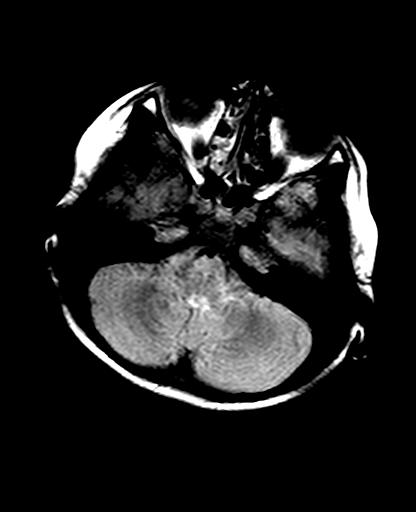

标题: PED2848:脑内病变2

头痛10天、间断呕吐2天。f 6岁

入科化验血清铜及铜兰蛋白均减低,脑脊液正常,血清神经原烯醇化酶明显增高。wbc:5.94x109/l、

临床表现及实验室检查符合肝豆状核变性

mri未见明显异常。但临床支持考虑肝豆状核变性。